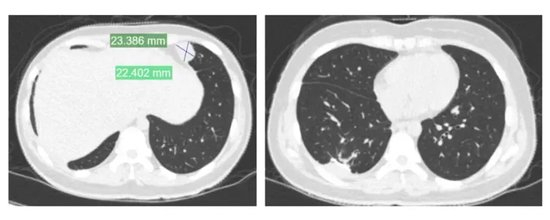

夏夏前期接受了术前化疗、截肢手术及术后化疗,使用的是一线化疗方案。然而,结疗不到一年,肺部出现转移病灶,经过手术切除后未再进行化疗。术后5个月,左肺再次发现新发转移病灶。

2024年11月,夏夏接受胸腔镜下右肺下叶切除术。2025年1月复查:右肺术后改变。